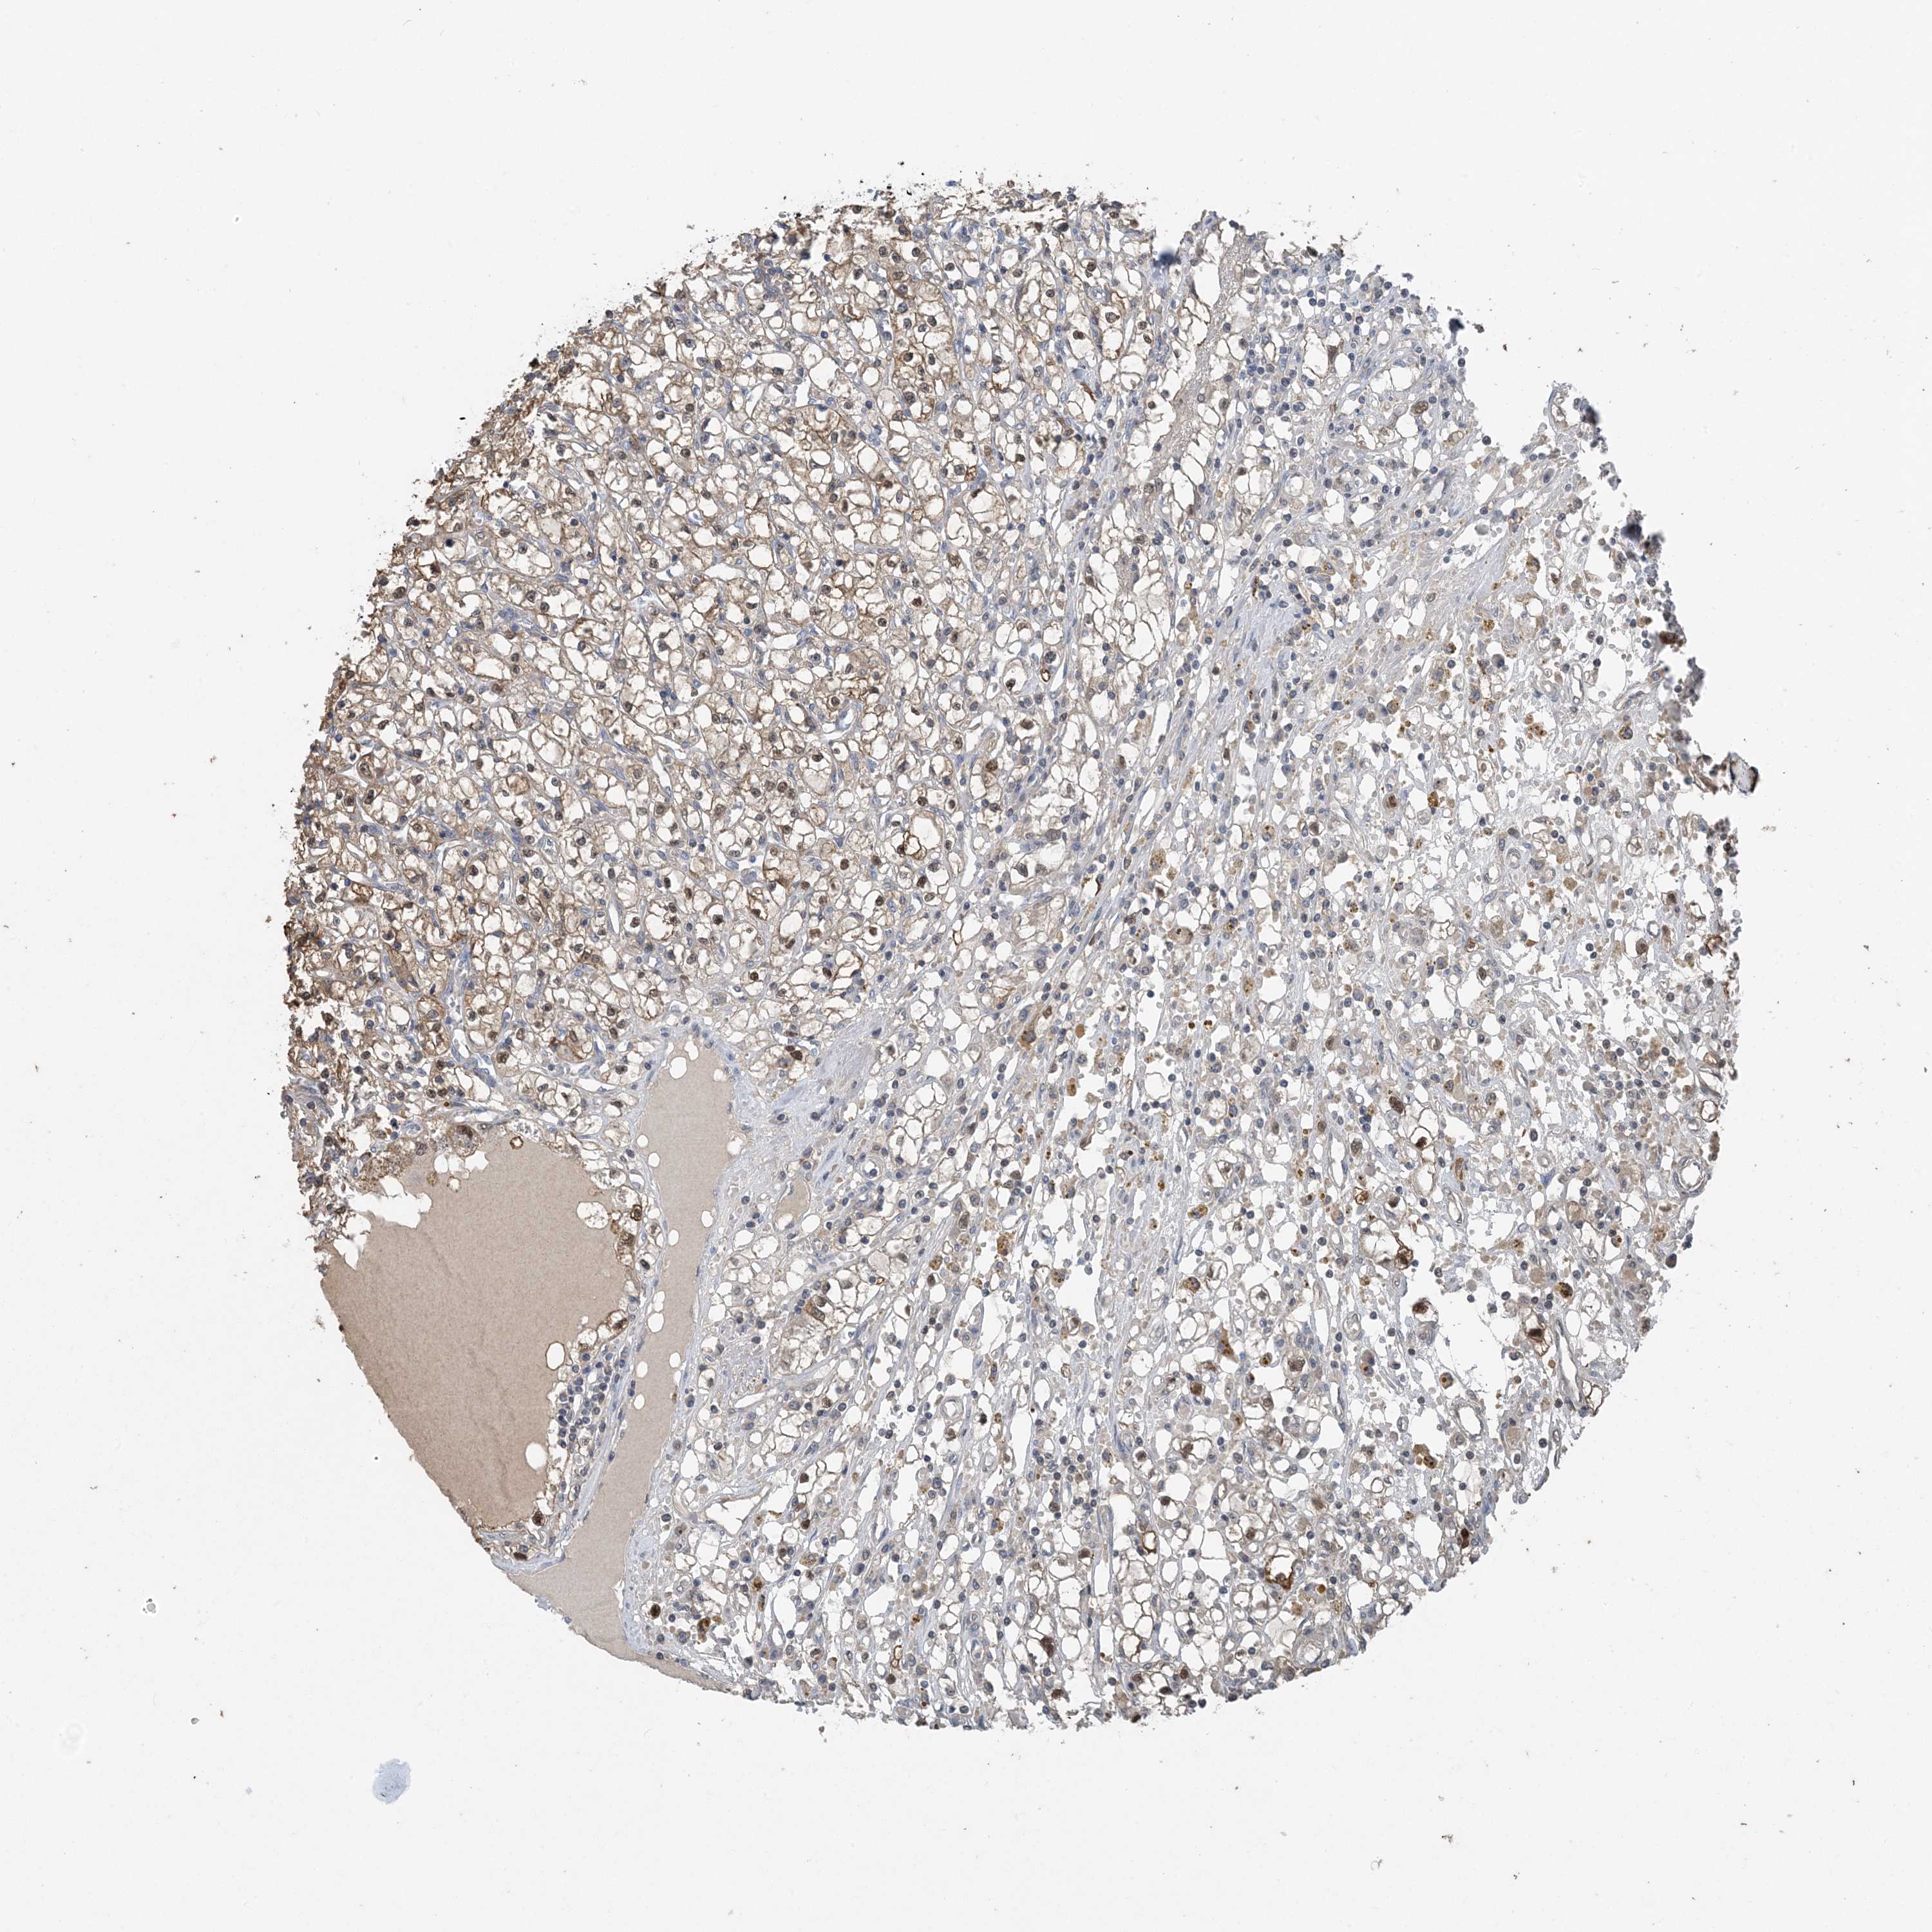

KIDNEY RENAL CLEAR CELL CARCINOMA (VALIDATION) - Interactive survival scatter ploti

The Survival Scatter plot shows the clinical status (i.e. dead or alive) for all individuals in the patient cohort, based on the same data that underlies the corresponding Kaplan-Meier plots. Patients that are alive at last time for follow-up are shown in blue and patients who have died during the study are shown in red.

The x-axis shows the expression levels (FPKM) of the investigated gene in the tumor tissue at the time of diagnosis. The y-axis shows the follow-up time after diagnosis (years). Both axes are complimented with kernel density curves demonstrating the data density over the axes. The top density plot shows the expression levels (FPKM) distribution among dead (red) and alive patients (blue). The right density plot shows the data density of the survived years of dead patients with high and low expression levels respectively, stratified using the cutoff indicated by the vertical dashed line through the Survival Scatter plot. This cutoff is automatically defined based on the FPKM cutoff that minimizes the p-score. The cutoff can be changed by dragging the vertical line or by entering a cutoff value in the square labeled "Current cut-off".

Under the Survival Scatter plot the p-score landscape (black curve; left axis) is shown together with dead median separation (red curve; right axis). Dead median separation is the difference in median mRNA expression between patients who have died with high and low expression, respectively. It is calculated as follows: median FPKM expression of dead patients with high expression - median FPKM expression of dead patients with low expression. This is intended to aid the user in visually exploring custom cutoffs and the associated p-scores and dead median separation.

Individual patient data is displayed and can be filtered by clicking on one or more of the category buttons on the top of the page. Categories describing expression level and patient information include: high, low, alive, dead, female, male and tumor stages. The scale of the x-axis can be toggled between linear and log-scale by clicking on the "x log" button. Mouse-over function shows TCGA ID, patient information and mRNA expression (FPKM) for each patient.

& Survival analysisi

Kaplan-Meier plots summarize results from analysis of correlation between mRNA expression level and patient survival. Patients were divided based on level of expression into one of the two groups "low" (under cut off) or "high" (over cut off). X-axis shows time for survival (years) and y-axis shows the probability of survival, where 1.0 corresponds to 100 percent.

HIKESHI is potential prognostic, high expression is unfavorable in Kidney Renal Clear Cell Carcinoma (validation)

Best expression cut offi

Based on the FPKM value of each gene, patients were classified into two groups and association between prognosis (survival) and gene expression (FPKM) was examined. The best expression cut-off refers the FPKM value that yields maximal difference with regard to survival between the two groups at the lowest log-rank P-value. Best expression cut-off was selected based on survival analysis .

When clicking on this number, the vertical dashed line indicating cut-off, the interactive survival plot, and the Kaplan-Meier curve will be adjusted to show results based on the best expression cut-off.

: 26.78

Average pTPM 21.2

Number of samples 100